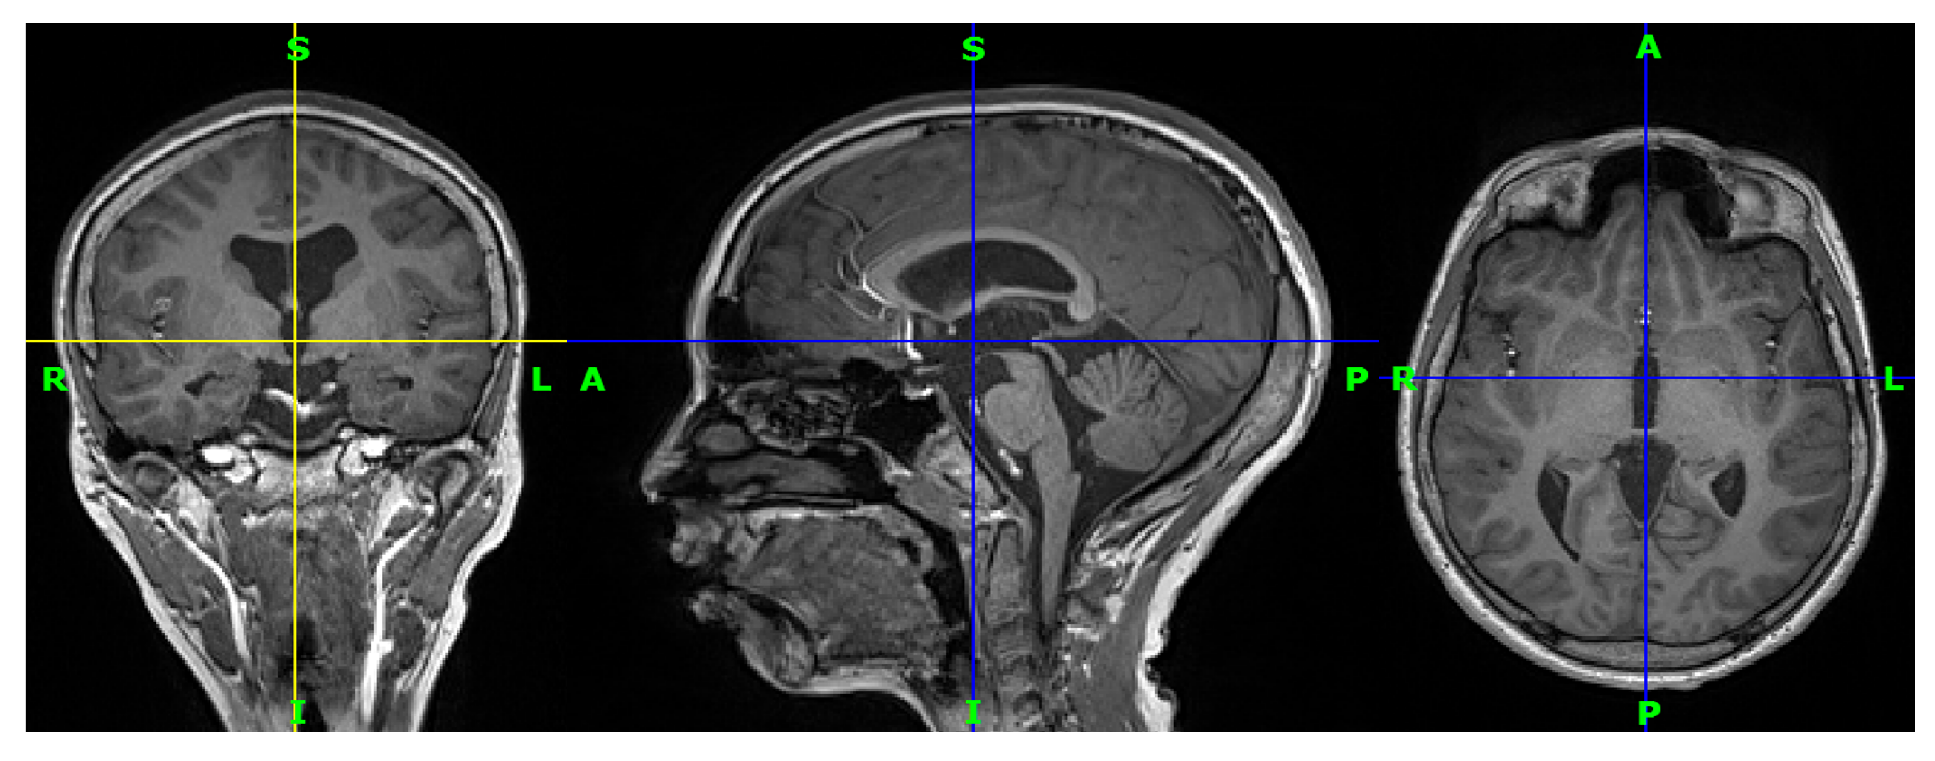

Figure 5.

Three-dimensional T1-weighted MRI for a patient from the data set in coronal view, sagittal view, and axial view, respectively. R indicates the right of the brain, L indicates the left of the brain, S (superior) indicates the top of the body, and I (inferior) indicates the bottom of the body.